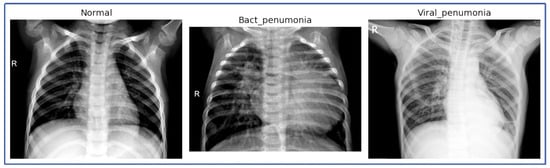

Figure 3 presents a series of CXR images categorized into three groups: NL, BP, and VP. The images reveal clear distinctions between the different conditions:

CXR images of NL, BP, and VP.

- Normal: The images labeled as ‘normal’ depict clear lung fields without any significant opacities or consolidations. The bronchial and vascular structures are visible and consistent with normal chest radiographs, which serve as a baseline comparison against the pneumonia-affected lungs.

- Bacterial Pneumonia: Several images labeled as ‘Bact_pneumonia’ exhibit prominent consolidation, with areas of opacity that suggest alveolar filling, which is characteristic of bacterial pneumonia. These radiographic findings are consistent across multiple images, highlighting the typical presentation of bacterial pneumonia.

- Viral Pneumonia: The ‘viral_pneumo’ images demonstrate more diffuse patterns, with less pronounced opacities compared to bacterial pneumonia. The images show peribronchial thickening and interstitial markings, which align with the expected radiological signs of viral infections.